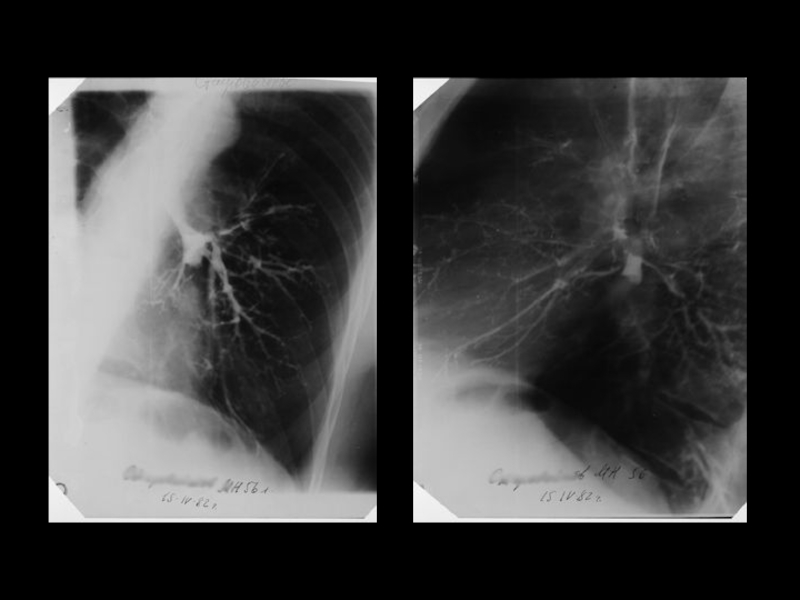

Центральный рак легкого

ЛУЧЕВАЯ ДИАГНОСТИКА РАКА ЛЕГКОГО